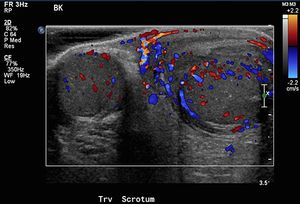

10-year-old male presents to the emergency department with left testicular pain and swelling for the last four days.